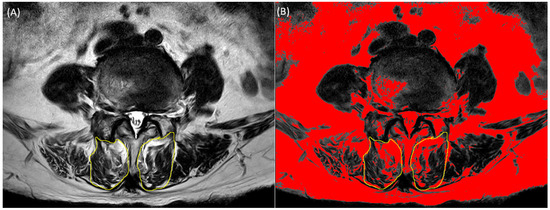

2.2. Multifidus Measurement from Spine MRI